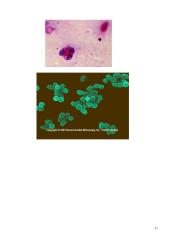

Morfologija.

• Gramneigiamos.

• Mažos 0,6-1,5x0,5-0,7.

• Žiuželiu neturi.

• Sporų nesudaro.

• Mikrokapsules sudaro tam tikros padermės.

• Nusmailėjusiais galais, kokų ar ovoidinės formos lazdelės.